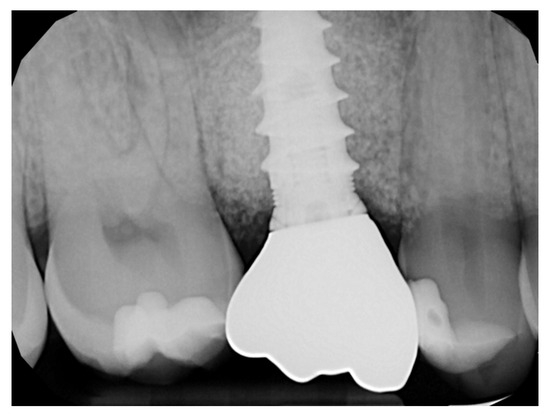

2.6. Case Presentation. Nano-HA Applied to Socket Preservation Procedures

3. Results